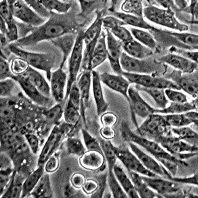

Морфология: эпителиоподобная

Способ культивирования: монослойный